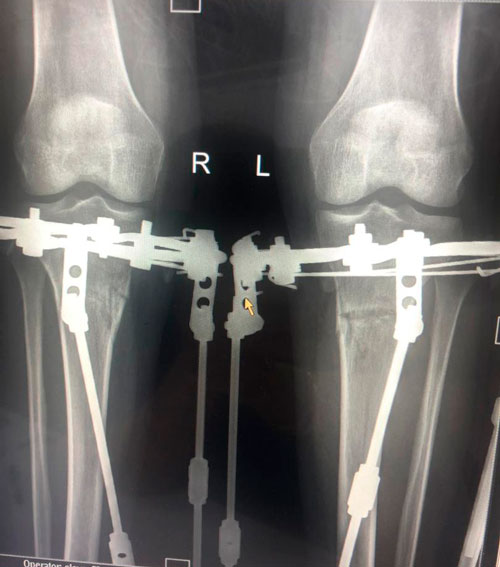

Дата операции -25.12.2018г.

Дата снятия аппаратов - 09.04.2019г.

Срок лечения 98 дней.